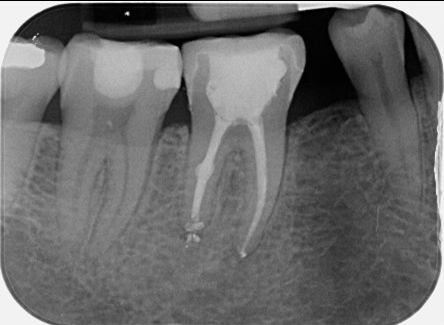

Root canal retreatment and bypass of separated instrument

Pre-op